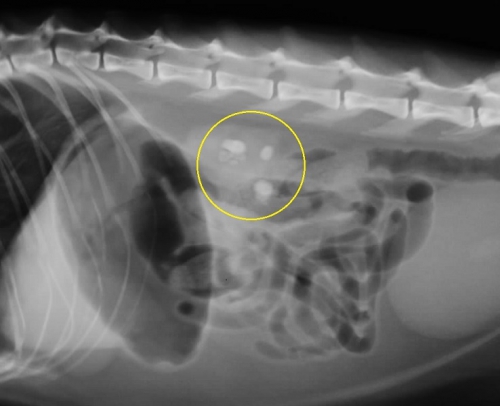

レントゲン検査により腎臓や尿管に結石が見つかった場合、さらに超音波検査によって結石の正確な位置関係とそれが周囲に及ぼす影響を評価します。下の2枚の写真は超音波検査の画像です。尿は左から右写真方向に「黒い管」として見える腎盂~尿管の中を流れます。

右下写真の黄色い円の中に見える「白いカタマリ」が尿管結石で、おおよそ3ミリくらいの直径があり、尿管を閉塞しています。

腎臓でつくられた尿がつまっているために尿管は重度に拡張しており、結石のすぐ上流で直径が4mm(赤矢印)、さらに腎臓の出口付近では1cm以上(緑矢印)にもなっており、腎臓内が拡張した水腎症になってしまっています。

通常では猫の尿管は極めて細いため超音波検査ではほぼ見ることができませんので閉塞の程度をイメージできるのではと思います。